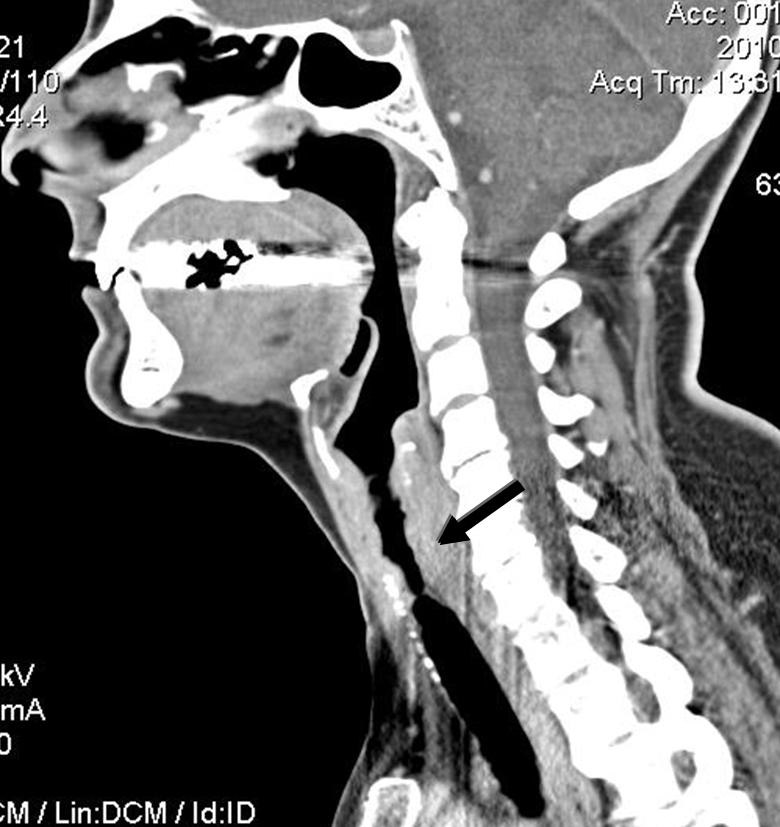

Figure 4

CT scan of the neck of a patient with GPA showing 6-cm-long subglottic stenosis (arrow).

The infra-glottic trachea is considered anatomically to be part of the lower respiratory tract. However, SGS, a rare but extremely challenging manifestation of GPA, is best managed by otorhinolaryngologists in collaboration with internists or rheumatologists for adjuvant systemic therapy. This manifestation was initially reported as affecting as many as 23% of patients. In more recent registry or cohort studies, such as the French, German or North American ones, the frequency is close to 3% to 9%. SGS occurs more frequently in women (female:male ratio 6:1) and in patients younger than average (i.e., approx. age 35 rather than 50) [32, 36, 39]. It is also a frequent manifestation in children with GPA. SGS can be isolated as the presenting or, rarely, the only manifestation of GPA [40]. The tracheal lumen can become significantly narrowed, a development which can be life-threatening. Obstruction can occur secondarily to acute inflammation due to suprainfection or detached crusts or scabs. Such cases may require urgent tracheotomy. To prevent this situation, physicians need a high level of suspicion and SGS must be included in the differential diagnosis for patients with GPA and dyspnoea or voice changes [41]. Such patients should be promptly evaluated by an otorhinolaryngologist. SGS may occasionally be associated with bronchial stenoses, which are even rarer than SGS but also potentially life-threatening, and in the majority of cases managed by respirologists.

SGS is best studied on CT scan (fig. 4 and 5) but must also be evaluated clinically by flexible nasolaryngoscopy. Interestingly, the lesion is usually segmental and located 1 to 2 cm below the vocal cords, probably because it represents the junction between 2 embryological buds or growth centres. Biopsy of the lesions can be revealing in more than half of cases, but endoscopy and biopsy of SGS may be risky in such patients. These invasive procedures can trigger a local inflammatory reaction, worsen the stenosis, and/or result in detached necrotic debris which is then inhaled, during the procedure itself or soon after. Spirometry may reveal blunting of the inspiratory curve, but the diagnosis should not rely solely on this modality.